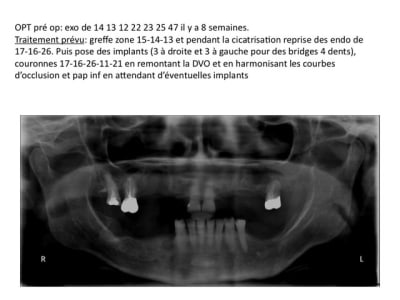

détail des fragments du prélèvement après découpe en 2

Au niveau mésial, le défaut osseux faisait comme une box dans laquelle ma baguette s'adaptait parfaitement. La première vis vient bloquer les deux baguettes et la second vient bloquer la baguette vestibulaire et empêcher tout mouvement.

Mon interrogation c'est plutôt en occlusal, comment éviter une colonisation conjonctive ?